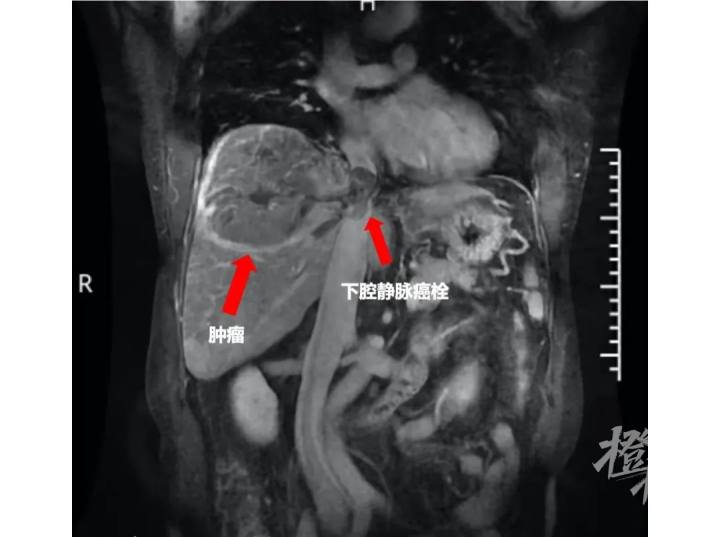

都市快报讯 一边是右肝如柚子大小的肿瘤,一边是“命脉”大血管中鸽子蛋大小的瘤子。四个月前,当李先生(化名)被告知肝癌晚期且伴有癌细胞入侵大血管已失去手术机会时,正值壮年的他感觉天要塌了。

“病情还是非常棘手的。”梁医师坦言,当时肿瘤本身已经十分巨大,且肝癌细胞已经“跑”到血管中,且在下腔静脉中聚集成团,形成鸽子蛋大小的“栓子”,两处肿瘤就如同身体内两颗“定时炸弹”,特别是下腔静脉癌栓已经离右心房非常近,随时可能脱落进入心脏,时刻都有可能危及生命。

“下腔静脉是联通心脏的最大静脉,全身三分之二的血液都要通过它流回心脏,这个位置就好比自来水出厂后的第一道管口,如果在这个血管上开口子取癌栓,后果可想而知,身体内的血液可能在几分钟的时间里就流干了。”梁霄主任解释说,在这个病例中,取栓是比切除肝癌更为艰难的一步。

经过大约两个半月转化治疗后,梁霄主任医师为李先生安排了住院检查。这时,肝脏的磁共振显示,肿瘤有明显缩小迹象,且下腔静脉里的癌栓也缩小了。